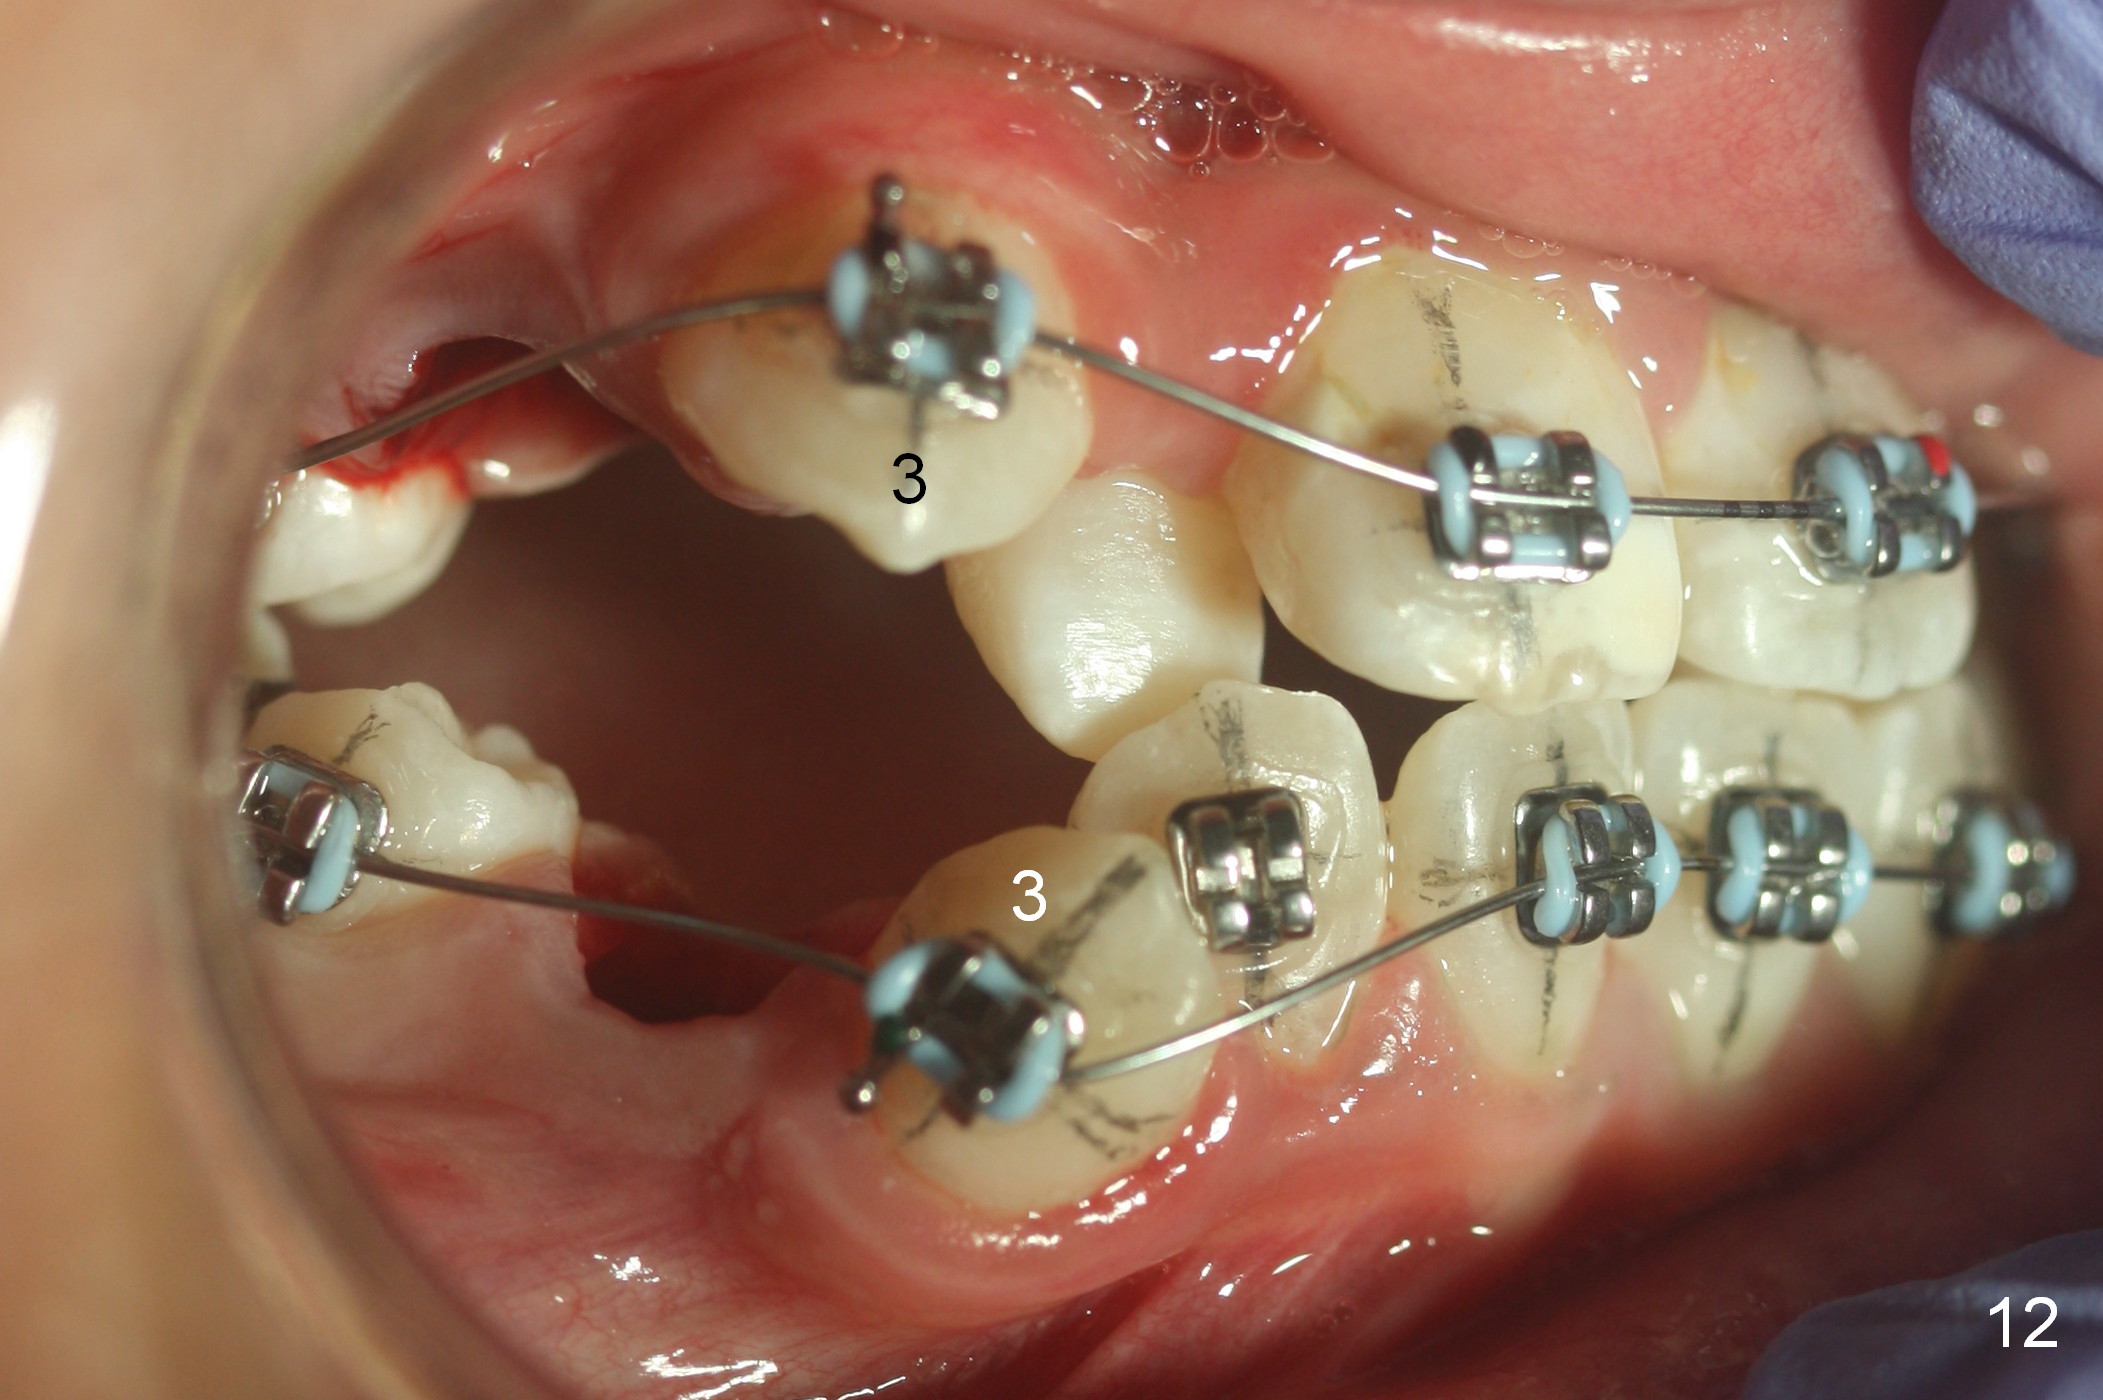

The right canines are blocked (Fig.6,9). Use an elastic between them as early as possible to facilitate eruption, which is not done immediately post banding and extraction of R4s (Fig.12 (.014' niti wires)).

One month post banding, the upper wire changes to .016', while the lower one remains .014' with LR2 bracket partially engaged (Fig.13). Intuitively, an elastic is placed between UR3 and LR3. It appears that these two teeth have been moved occlusally and distally quite a bit in 1 month.